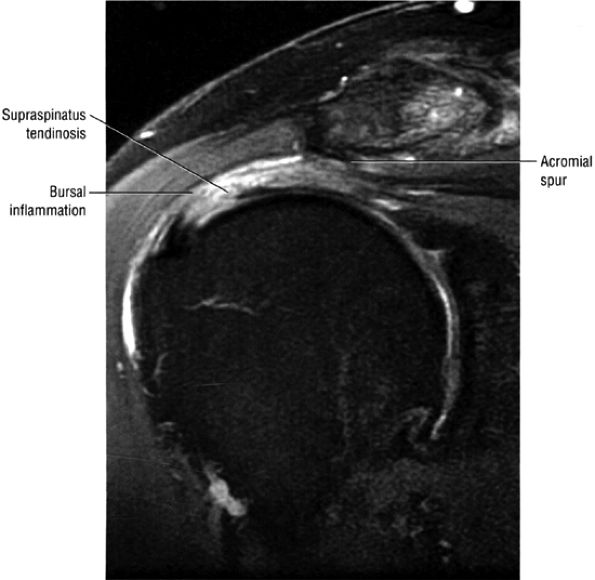

inferior surfaces of the acromion. The coracoacromial arch stabilizes the humeral head and prevents superior ascent (Fig. 8.102). The subacromial bursa is located between the acromion, the coracoacromial ligament, and the rotator cuff.44 The bursa runs from the AC joint medially, under the anterior third of the acromion and coracoacromial ligament, to a line that extends approximately 4 cm anterior and lateral to the anterolateral margins of the acromion. Anterior acromial spurs, caused by chronic irritation from the humerus in contact with this ligamentous structure, may form within the acromial portion of the coracoacromial ligament.46 Frequently, anterior acromial spurs are identified adjacent to the acromial attachment of the coracoacromial ligament. The normal low-signal-intensity acromial attachment of the coracoacromial ligament is frequently mistaken for an anterior acromial spur on coronal oblique MR images. The additive thickness of the coracoacromial ligament and the inferior acromial cortex produces this pseudospur (Fig. 8.103). In acromioplasty performed for chronic impingement, the coracoacromial ligament and the anterior inferior margin of the acromion are resected.